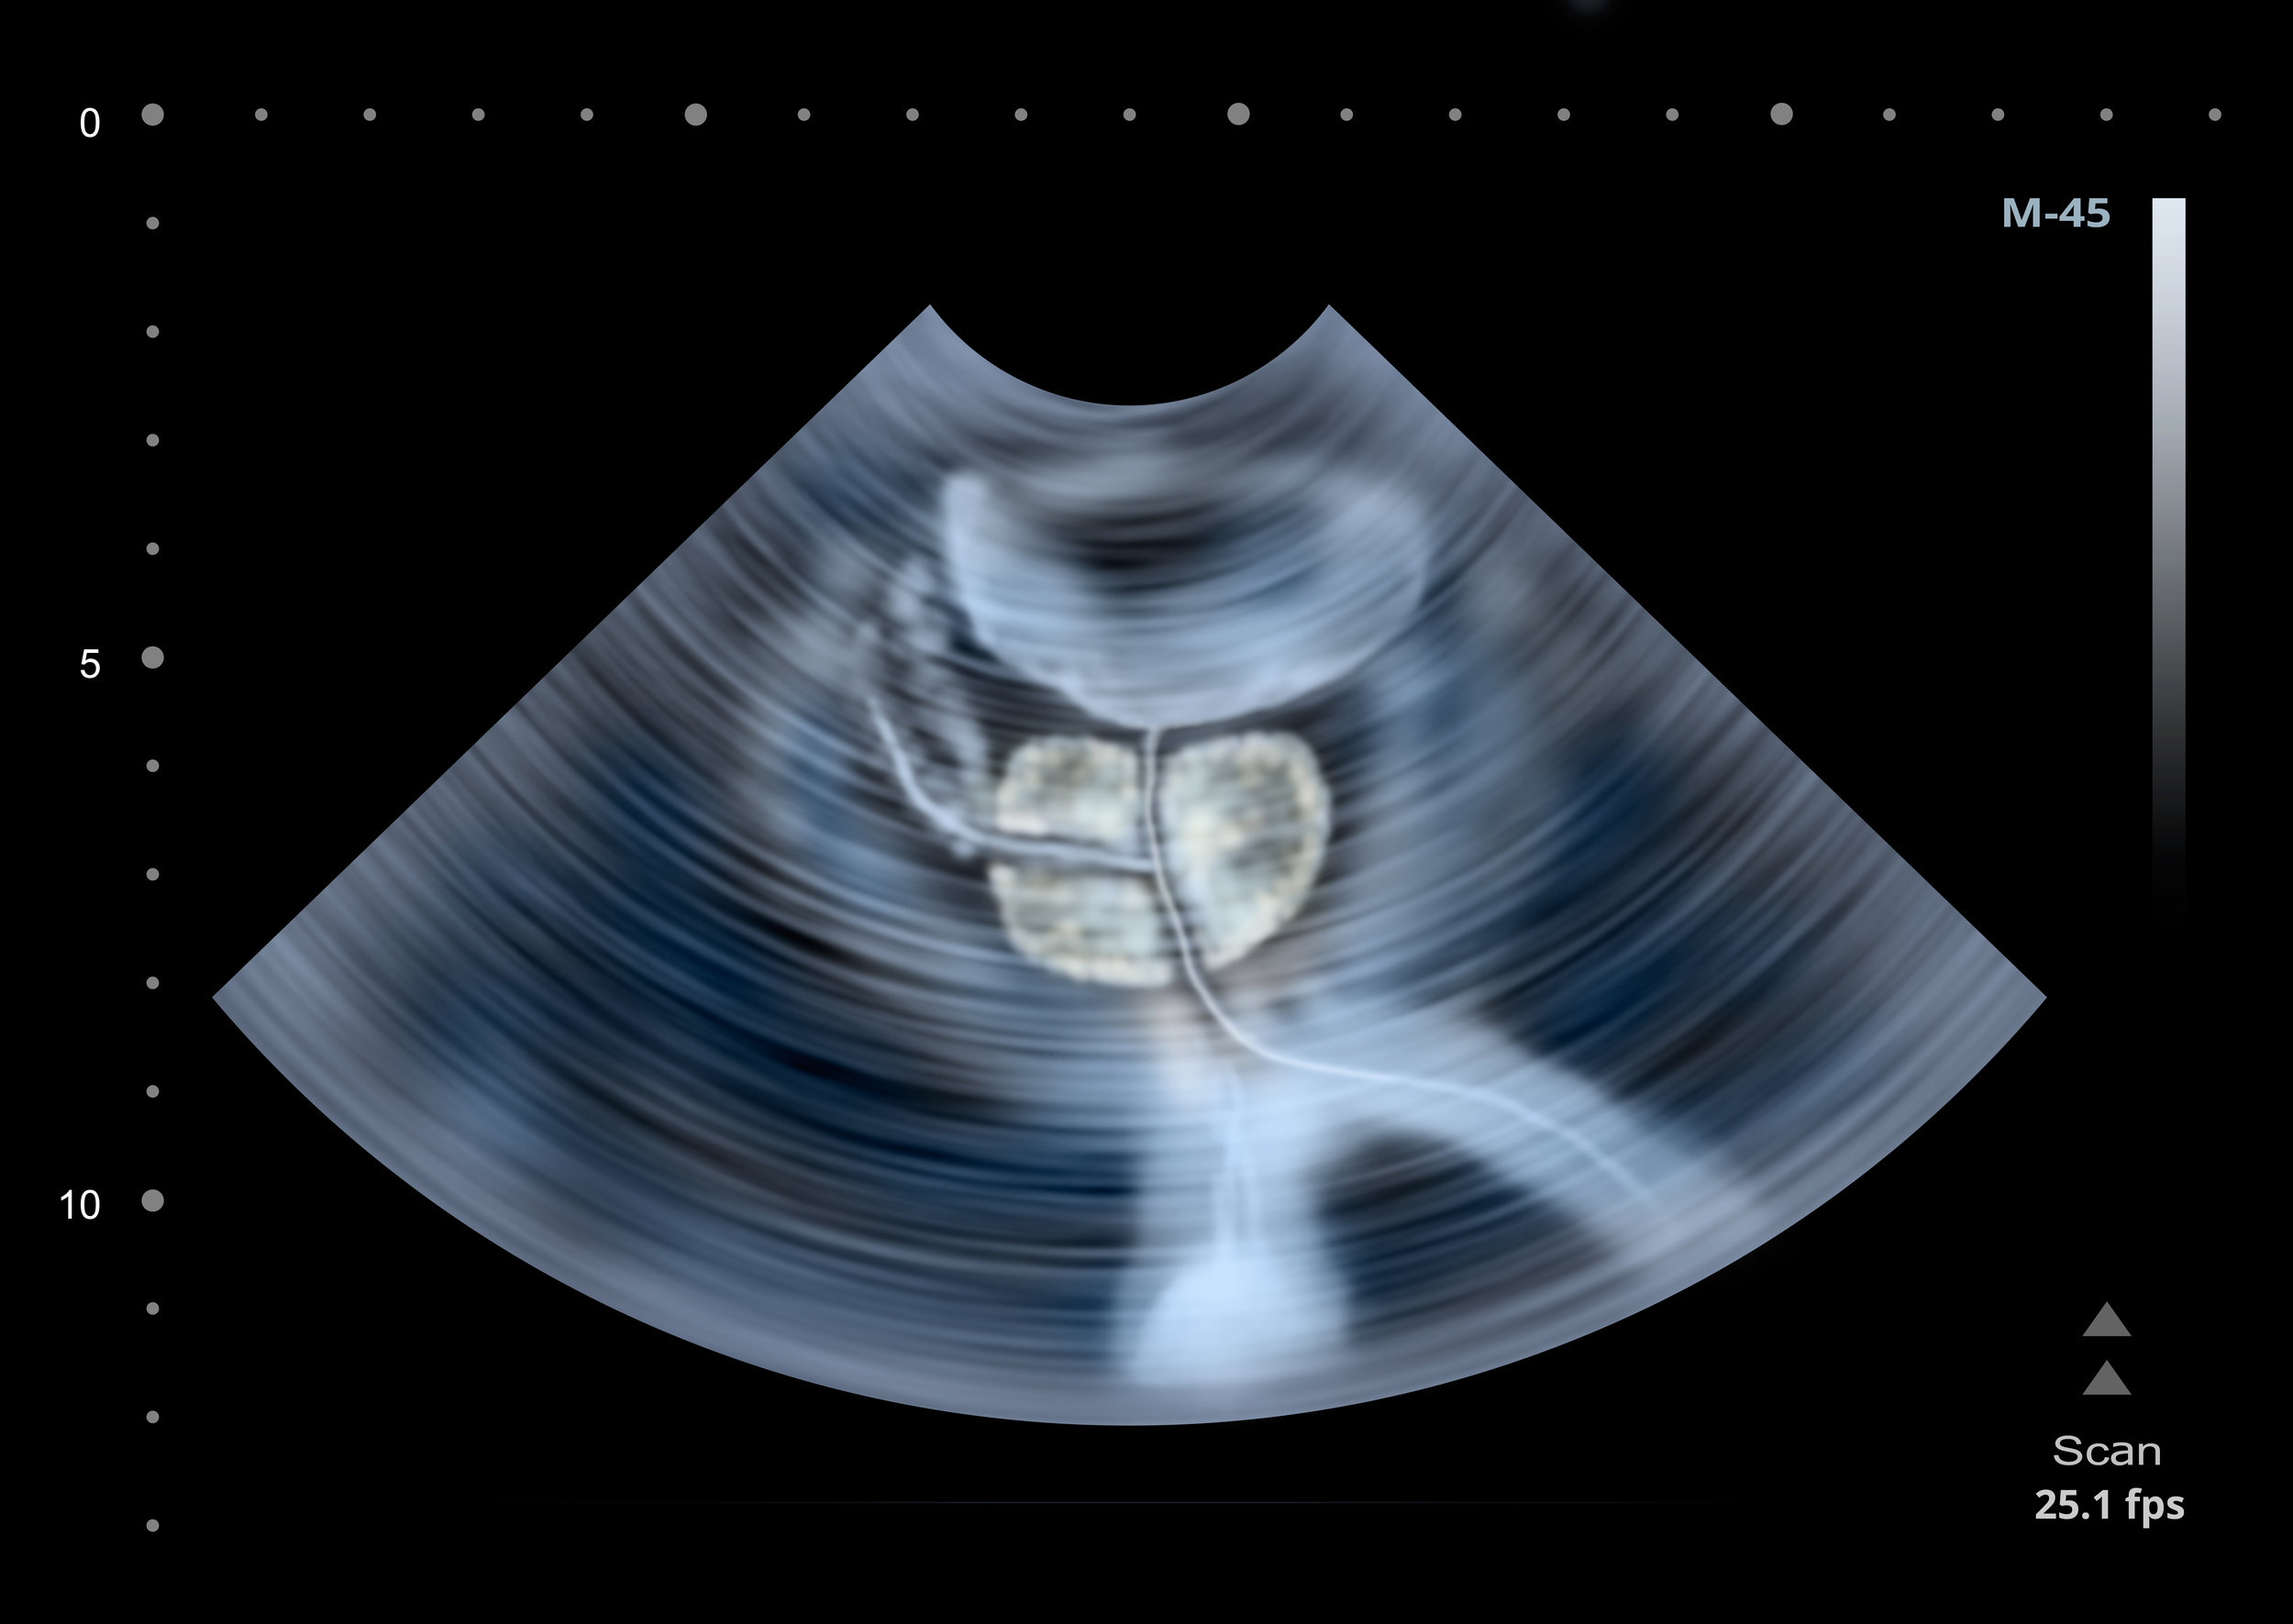

Some doctors may recommend using the standard prostate cancer screening tests of the blood test for PSA, a digital rectal exam, transrectal ultrasound, and looking into family history of prostate cancer to evaluate the risk of progression. But the issue with this is the test does not reliably help identify men who have high-grade PIN and who will go on to develop prostate cancer.